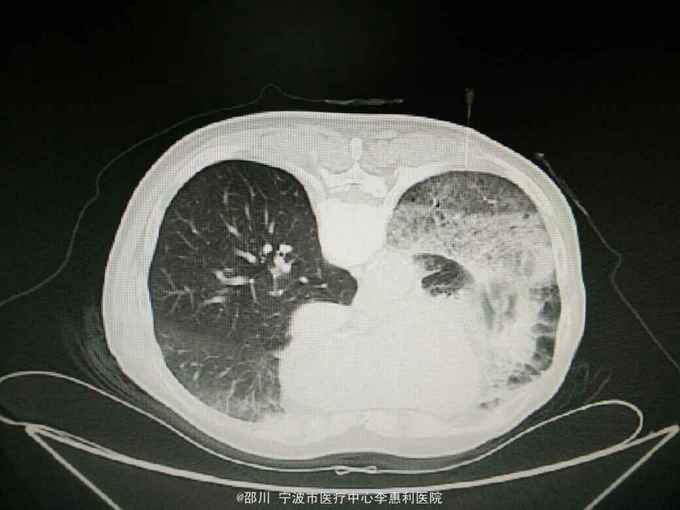

查体:神志清,精神好,生命体征平稳。两肺呼吸音清,未闻及干湿啰音。 辅查:血常规:WBC 9.0×10^9/L,NE 65.1%, Hb 152g/L, plt 246×10^9/L。血CEA 41.6ug/L。小便常规,大便常规,凝血功能,D-二聚体,肝肾功能,电解质均无明显异常。心电图,腹部B超无异常。 2015-10-30我院胸部CT见下图。